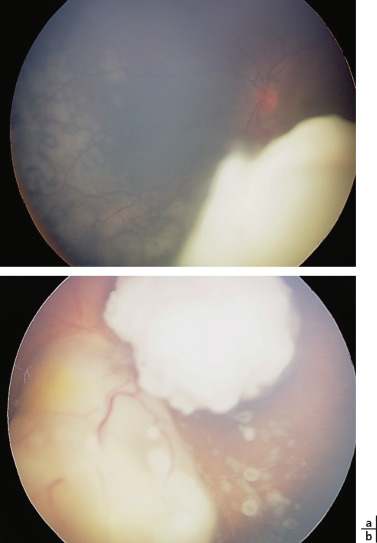

L’aspect des tumeurs peut être variable mais la plupart du temps, il est caractéristique et le diagnostic de rétinoblastome est clinique. Il s’agit de lésions tumorales rétiniennes blanches dont le nombre est variable et pouvant contenir des calcifications (fig. 20-18). La masse tumorale peut être plus ou moins importante : lorsque la masse est très volumineuse, elle est souvent associée à un DR exsudatif. Dans le cas des dépistages systématiques des enfants à risque, des lésions parfois millimétriques sont détectées (fig. 20-19). Un essaimage tumoral sous-rétinien (fig. 20-20a) ou intravitréen (fig. 20-20b), dont la présence et l’étendue sont un facteur de moins bon pronostic de conservation oculaire, peut s’associer à la masse tumorale.

Fig. 20-20  Essaimage tumoral à distance de la tumeur rétinienne.

a. Essaimage sous-rétinien à distance d’un volumineux rétinoblastome. b. Bulles d’essaimage vitréen associées aux tumeurs rétiniennes.